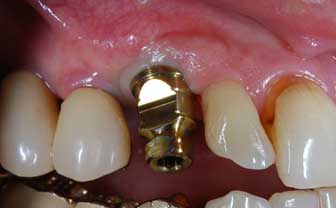

I denti irrecuperabili dell'arcata superiore ed inferiore del paziente di anni 65

sono stati sostituiti da 10 impianti, cioè protesi radicolari endo-ossee che sostengono le protesi fisse superiore ed inferiore.